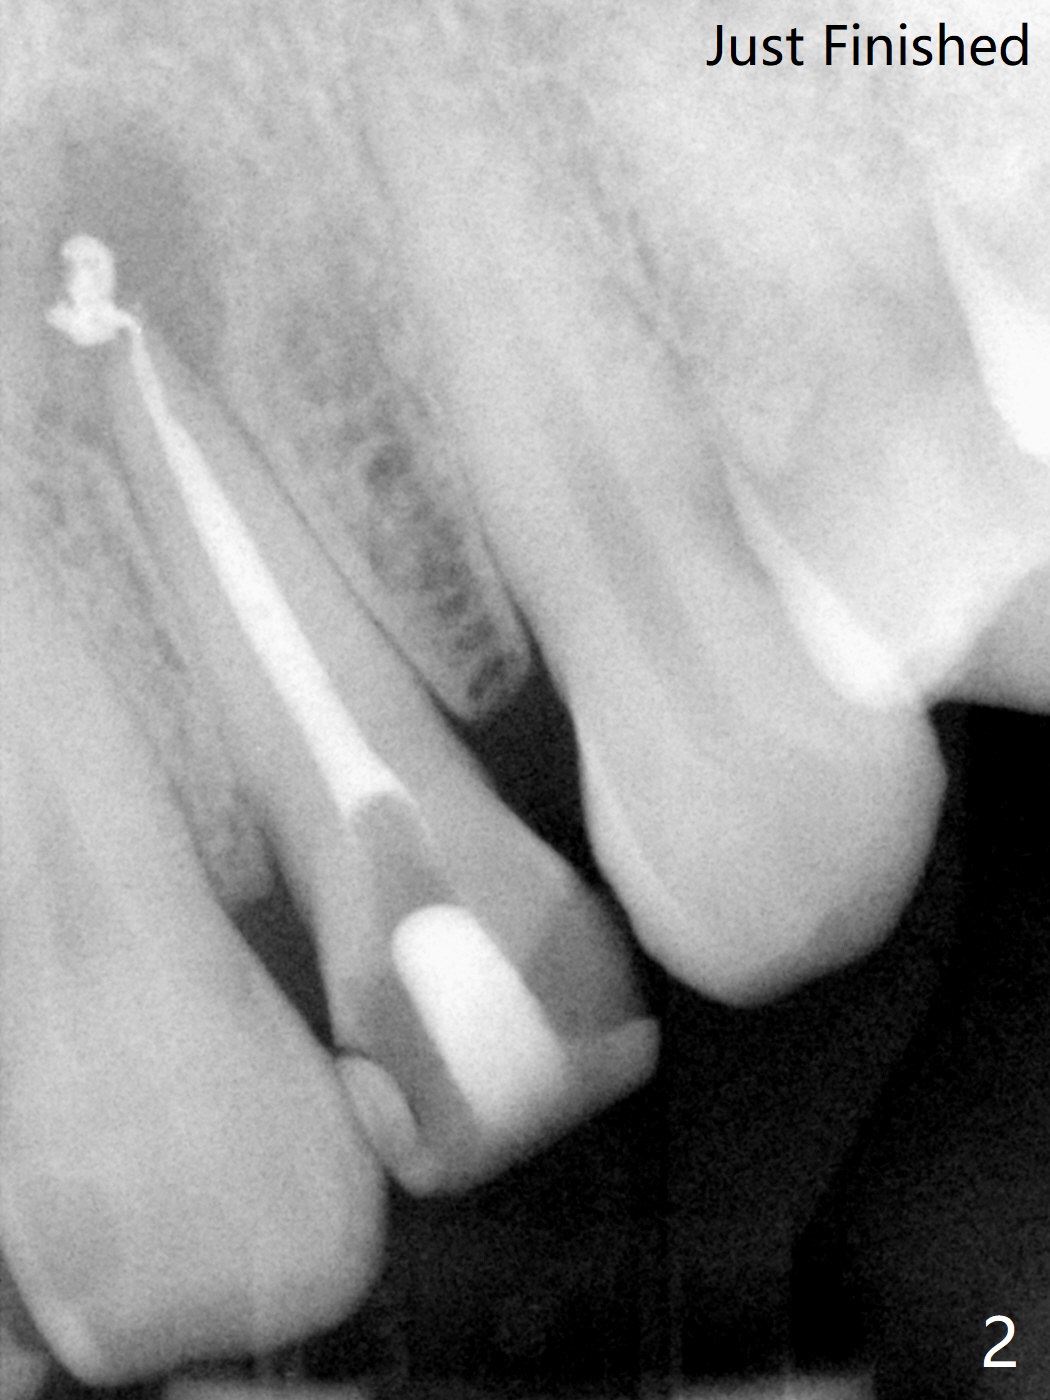

A 47-year-old woman with multiple restoration has PARL at #10 (Fig.1 *). RCT is done with paste leakage (Fig.2). PARL reduces and disappears 2.5 and nearly 10 years postop (Fig.3,4).